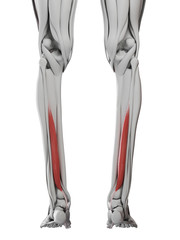

Podobny obraz Medical Elbow Anterior View X-Ray Radiograph Illustrating...